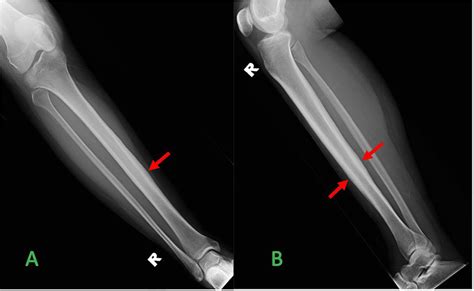

Alright, let’s get to the main event: the pseudoarthrosis tibia X-ray. This is the go-to imaging tool for docs trying to figure out if you’ve got this non-union thing going on. When they suspect pseudoarthrosis, the standard X-ray is usually the first step, and often, it’s enough to give them a pretty good idea. What are they actually looking for on these films, you ask? They’re hunting for signs that the bone hasn’t knitted back together . A healthy fracture healing will show progressive callus formation – that’s new bone trying to bridge the gap. In pseudoarthrosis, you’ll often see a clear gap between the broken bone ends, and instead of solid bone bridging it, there might be fibrous tissue or even cystic changes in the bone ends. Sometimes, the bone ends can become rounded off and sclerotic (that means hardened and denser) because they’re not being used properly, and the body’s trying to adapt to the instability. Another key indicator is motion at the fracture site . While you can’t directly see motion on a static X-ray, the consequences of that motion are visible. You might see widening of the fracture line over time, or displacement of the bone fragments that wouldn’t happen if the bone were solidly healed. They’ll also look at any hardware – like screws, plates, or rods – that might have been put in during initial surgery. Is the hardware intact? Is it loose? Is there any sign of infection around it (like bone resorption or bone spurs)? The X-ray is basically a detective’s magnifying glass, revealing clues about the past injury and the body’s current, failed attempt at repair. It’s essential to compare current X-rays with previous ones if available, as this allows the radiologist and orthopedic surgeon to track the progression (or lack thereof) of healing over time. This comparison is vital in confirming a diagnosis of pseudoarthrosis, as a single X-ray might not always be definitive, especially in the early stages of non-union.

What Radiologists Look For on a Pseudoarthrosis Tibia X-Ray

Radiologists are like the skilled detectives of the medical world when it comes to interpreting X-rays. For a pseudoarthrosis tibia X-ray , they’re scrutinizing the image with a fine-tooth comb. The primary goal is to identify lack of bony union . This means they’re looking for a distinct gap between the fractured bone ends. In a successfully healing fracture, this gap would be filled with callus, a new bone formation that gradually ossifies. In pseudoarthrosis, this callus is either absent, inadequate, or has failed to mature into solid bone. They will specifically look for atrophic changes , which means the bone ends are thin, pointed, or have lost their normal shape due to disuse and lack of stability. Conversely, they might see hypertrophic changes , where the bone attempts to heal by forming excessive, often disorganized, bone spurs (callus) around the ends, but these spurs don’t actually bridge the gap. This is often called